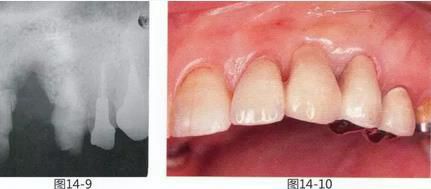

圖14-7  對移植瓣進行修整并放入受皮側,進行縫合固定。

圖14-8  術后1年2個月。對臨時橋體部的形態(tài)進行修整,對齊牙槽嵴的形態(tài)。

圖14-9   取模時的X光片。很明顯愈合的不是硬組織而是軟組織。

圖14-10 佩戴最終橋冠時。